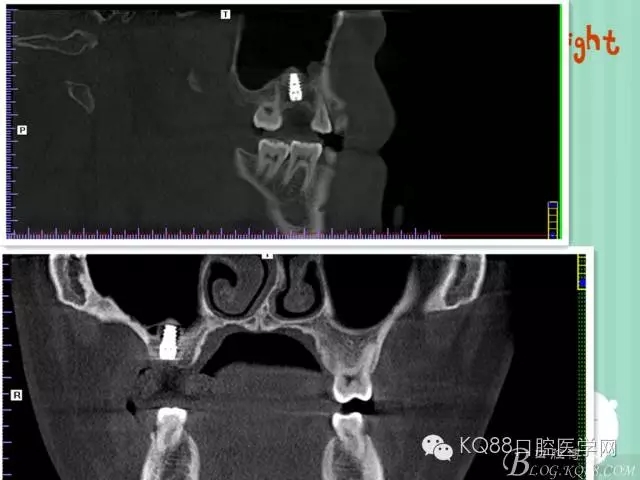

植入后,CBCT

另外一個切面。竇底粘膜完整連續(xù)。可以看到上下咬合的位置關(guān)系。

下面兩張是種植前后的對比片子。

手術(shù)前

手術(shù)后。